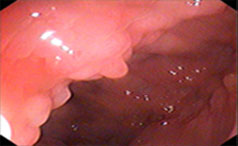

慢性胃炎系指不同病因引起的各种慢性胃黏膜炎性病变,是一种常见病,其发病初期症状不太明显,很多患者在无症状期间忽......【详情】

常见症状:恶心呕吐、食欲减退

餐后饱胀、反酸嗳气

常见症状:胃胀、胃脘痛、贫血、烧心

消化不良、大便异常、虚弱